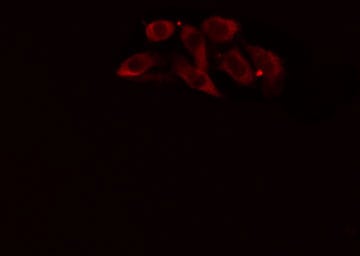

Enzyme-linked immunosorbent assay for Antigen Detection.